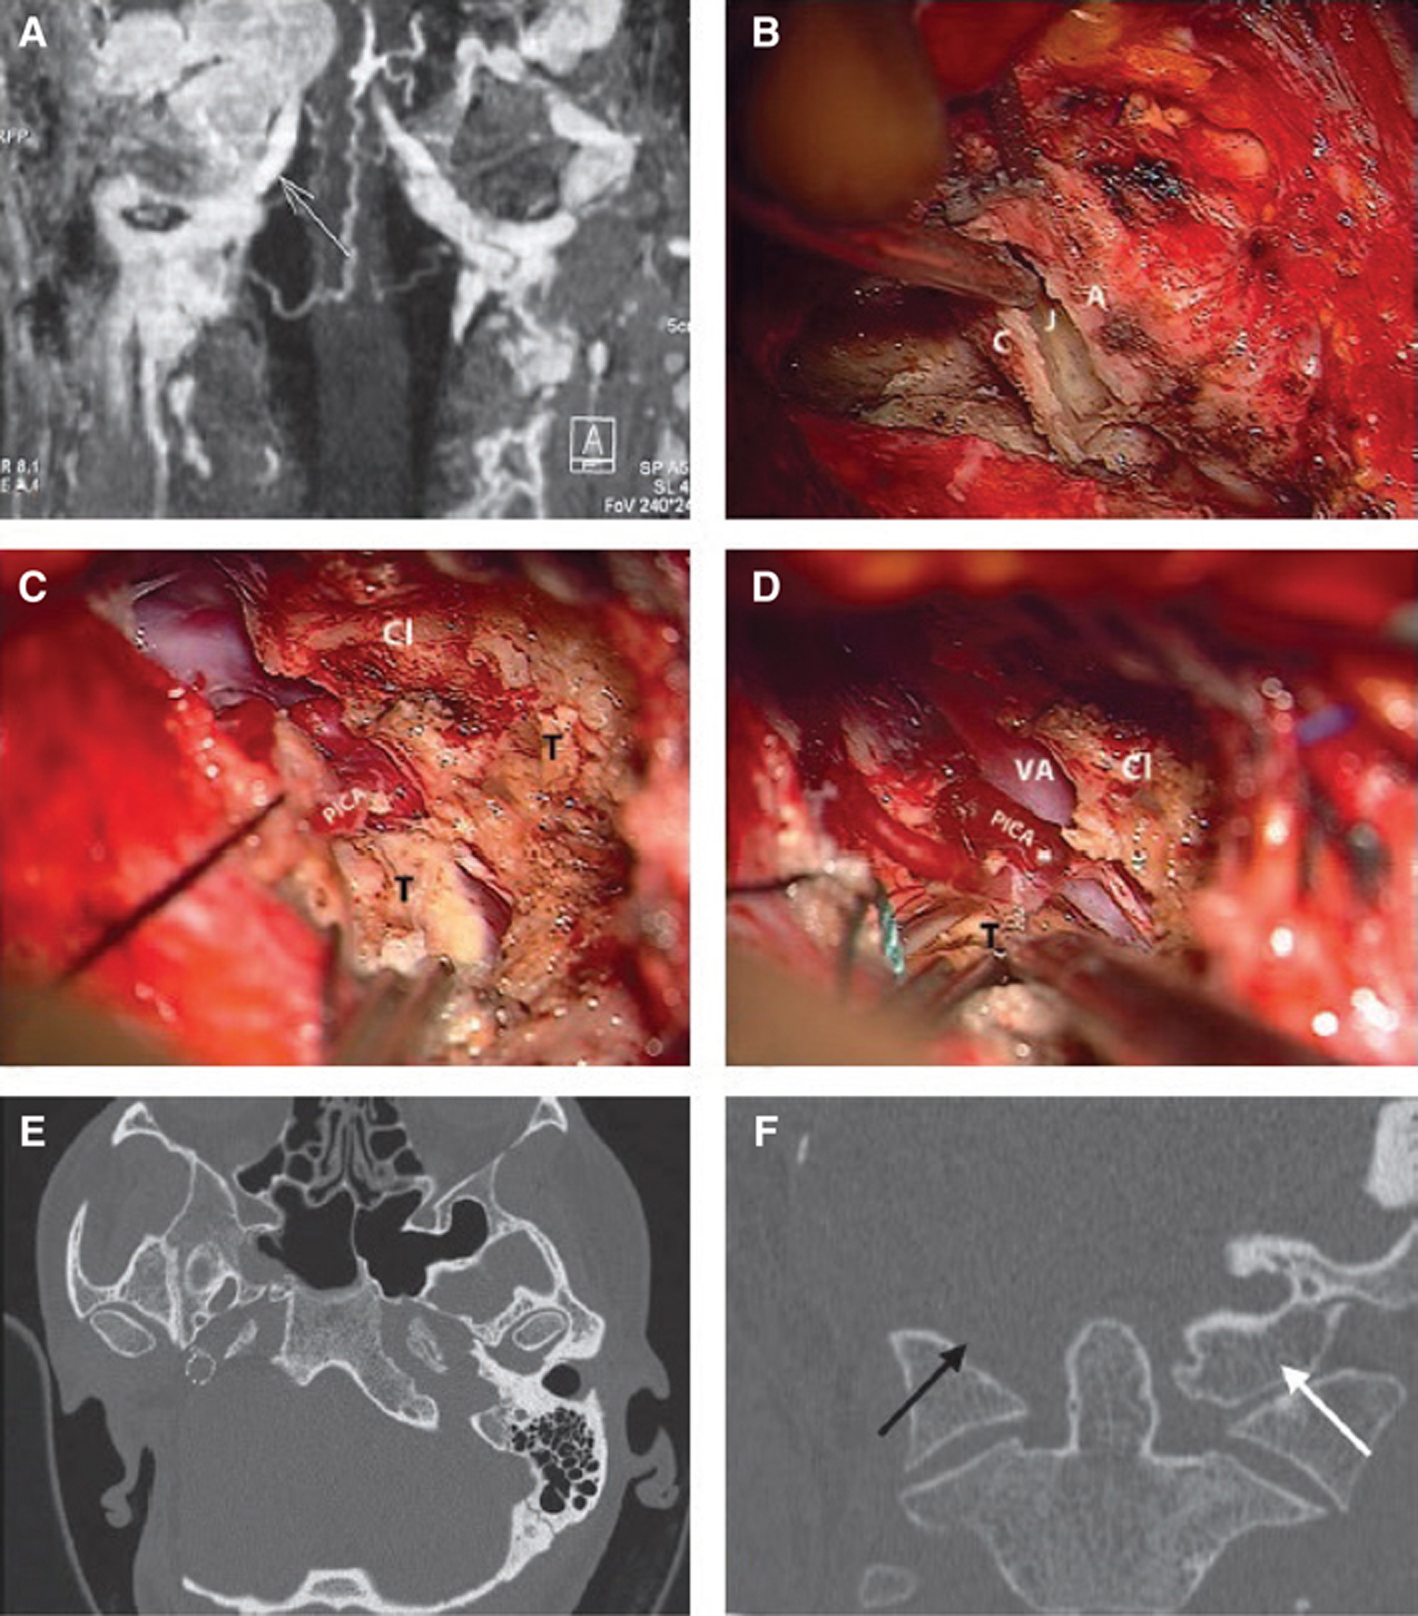

Fig 7

Figure 7 (A) A class C4Di2Vi tumor. MRI coronal image showing the tumor attached to the VA. (B–F) Surgical sequences of extreme lateral transcondylar approach. (B) The transverse process of the atlas (A) is drilled out and the atlanto-occipital joint (J) is removed. C = Condyle. (C) The tumor (T) is attached to the vertebral and posteroinferior cerebellar arteries infiltrating the clival (Cl) bone, which is partially drilled out. (D) The tumor is separated from the PICA. (E) CT scan. Axial view showing the stent in the ICA and the extent of bone removal. (F) CT scan coronal view showing the absence of the surgically removed occipital condyle (black arrow) compared to non-operated side (white arrow).

TJPs involving the VA are extremely uncommon. Only 11 cases were reported worldwide, of which eight belong to our series. We emphasized the importance of vertebral artery involvement in paragangliomas by introducing a “V” Class to the Fisch classification (2). Therefore, the vertebrobasilar system must always be included in the angiographic assessment of TJPs planned for surgery. Apart from the assessment of the VA directly, this is also useful for detecting anastomotic connections between the external carotid and the VA, which are potentially dangerous during embolization (48). The involvement of the V3 segment of the VA requires the employment of an extreme lateral extension to standard ITFA-A. As mentioned above, we prefer two-stage surgery in the case of large intradural extension (Figure 7A–F).